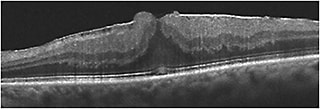

With careful clinical observation, most of the entities above can be accurately identified prior to ancillary testing. In practice, the most common entity that falls under the label of MPH is an ERM with invaginated foveal tissue (Figure 2). The OCT findings with this subtype of ERM include2 invaginated or heaped foveal edges, concomitant ERM with central opening, steep macular contour to the central fovea with near-normal central foveal thickness, and no loss of retinal tissue.

Figure 2. OCT of ERM with invaginated foveal tissue. Clinically, the eye would be in the category of macular pseudohole. Note that all retinal layers are intact.

For many years, LMH was not considered to be surgically amenable. Recently published studies have revealed that visual improvement can be achieved in some eyes with LMH; however, the visual improvement rate and ultimate visual function appear less robust than with ERM or even FTMH (Figure 3).

Figure 3. A 53-year-old man with progressively decreasing vision to 20/60 in the right eye associated with ERM and lamellar hole.